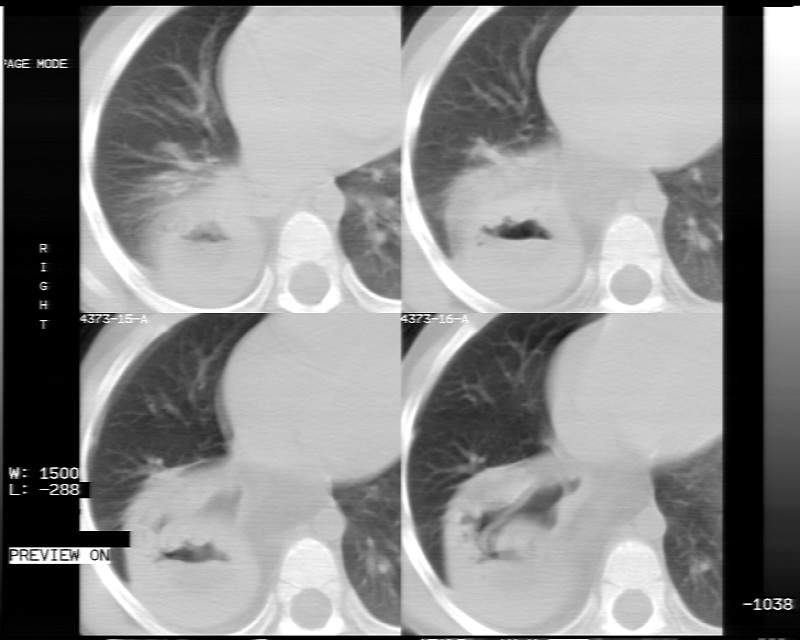

男性,3岁,斜疝术前常规检查胸片体检发现右下肺病变。咳嗽,无发烧。

建议mpr三维重建图像,冠状位看看。

内有气体,液平面,考虑食管裂孔疝可能性大。建议食道钡透。

有液气平面,前部肺纹理聚集(受压改变),周围肺野及相邻胸膜清晰,支持膈疝,可吞服造影剂看一下。

考虑膈疝(右侧胸腹膜裂孔疝?)。